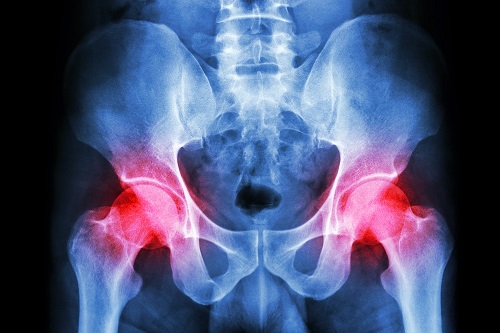

Kalça ağrısı neden olur nasıl geçer. Ağır spor yapmak ani hareket fazla kilolar ağır kaldırmak gibi birçok sebep kalça ağrılarına neden olmaktadır. Kalça ağrısının bulunduğu bölgeye buz kompresi uygulamak ağrıyı durdurmada etkili olabilir. Sıcak kompresin sıcaklığı bölgeyi rahatlatacak ve iyileştirecektir. Diz ve kalça romatizması ve diğer eklemlerdeki kıkırdak tahribatı son yılların en önemli.

Ağrının olduğu bölgeye masaj yapılması da oldukça etkilidir. Kalça ağrısı neden olur nasıl geçer. Kalça eklemi ağrıları gündelik hayatta pek çok insanın başına gelebilen bir rahatsızlıktır. Kalça ağrıları kişiden kişiye değişkenlik sağlayabilmektedir.

Kalça ağrınız yeni başlamışsa yüzmek bisiklete binmek veya yürümek gibi hafif egzersizler yapın. 2 3 saatte bir 10 15 dakikalık buz uygulaması ağrıyı hafifletebilir. Bununla beraber kalça kemikleri arasında bu eklemleri korumak için yastık görevi gören bir kıkırdak tabakası bulunmaktadır. Kan damarlarını açmaya yardımcı olur ve bu da kanın vücutta daha kolay dolaşıp besin maddelerini dağıtmasını sağlayarak toksinleri vücuttan atar.

En büyük ekleme sahip olan kalça bölgesi neredeyse her harekette kullanılmaktadır.